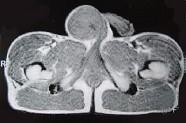

29岁男性患者,右侧睾丸肿痛5个多月,行MRI检查,如图所示,T1加权见右侧阴囊内见球形肿块,呈中等信号,其内信号不均,T2加权肿块为高信号,最可能的结果...

问题 29岁男性患者,右侧睾丸肿痛5个多月,行MRI检查,如图所示,T1加权见右侧阴囊内见球形肿块,呈中等信号,其内信号不均,T2加权肿块为高信号,最可能的结果是()

选项 A.精原细胞瘤 B.睾丸结核 C.畸胎瘤 D.皮样囊肿 E.畸胎癌

答案 A